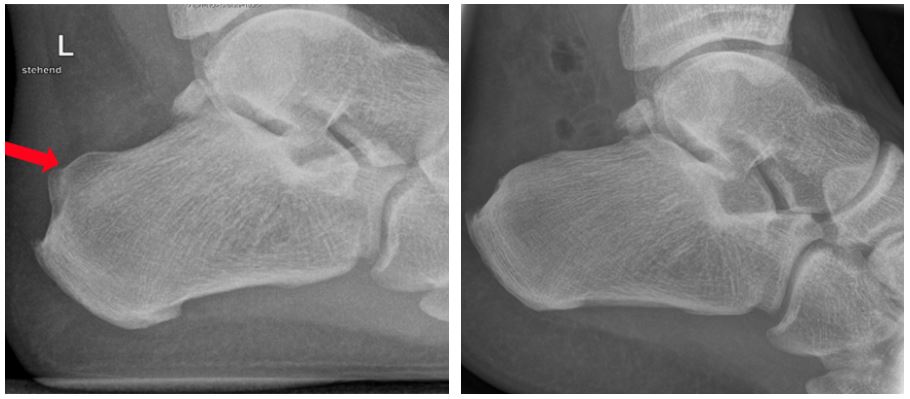

Bildgebende Diagnostik

Ein Röntgenbild des Fußes oder des Fersenbeines im Stand seitlich zeigt dann den vergrößerten Fersenbeinhöcker. Bei V.a. eine Achillessehnenreizung und eine Schleimbeutelreizung können auch eine Sonografie oder eine MRT ergänzend durchgeführt werden.